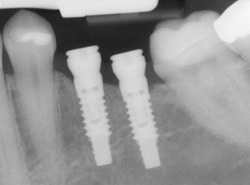

Implants are versatile. If you are missing only one tooth, one implant plus one replacement tooth will do the trick. If you are missing several teeth in a row, a few strategically placed implants can support a permanent bridge (a set of replacement teeth).

If you have lost all your teeth, a full bridge or full denture can be permanently fixed in your mouth with a strategic number of implants.